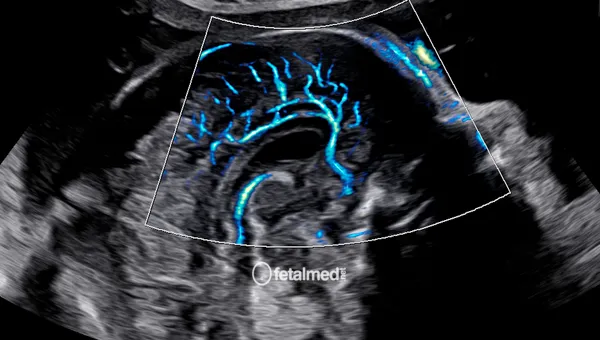

Ecocardiografia Fetal

Ecocardiografia fetal com Doppler colorido para avaliação detalhada do coração do bebê. Diagnóstico de cardiopatias congênitas em Curitiba.